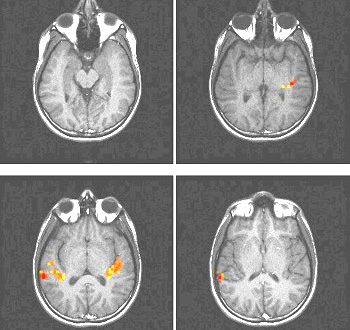

To date, several tasks have been utilized for mapping the brain cortex. Simple tasks include stimuli based on presentation of light, colors, tones, chords, music, syllables, movement of fingers and basic sensory perceptions. More complex and refined experiments have been implemented to map subtle cognitive functions. Currently, there is a vast armamentarium for mapping memory, attention, inhibition, face recognition, sensory discrimination, fear, etc.

However, most fMRI work has been directed in mapping language. Language mapping has been performed in children and adults. Reading, listening to meaningful text, generating words, making semantic decisions, are the most frequent paradigms described in the abundant current literature on fMRI. The technique has received ample acceptance among neuroscientists interested in epilepsy for the potential it has to become a tool to replace the Wada test.

Functional MRI is based on small signal changes that result from the following cascade of events. A task elicits activation in one or several brain areas. These areas increase their metabolic demands, suffer vasodilatation, and alter their levels of deoxyhemoglobin and oxyhemoglobin. Since deoxyhemoglobin is a paramagnetic molecule, it influences the phase of local proton-spins, altering the source signal that is converted into images. Therefore, the image is a representation of local changes of levels of deoxyhemoglobin, related to the brain region performing a task.